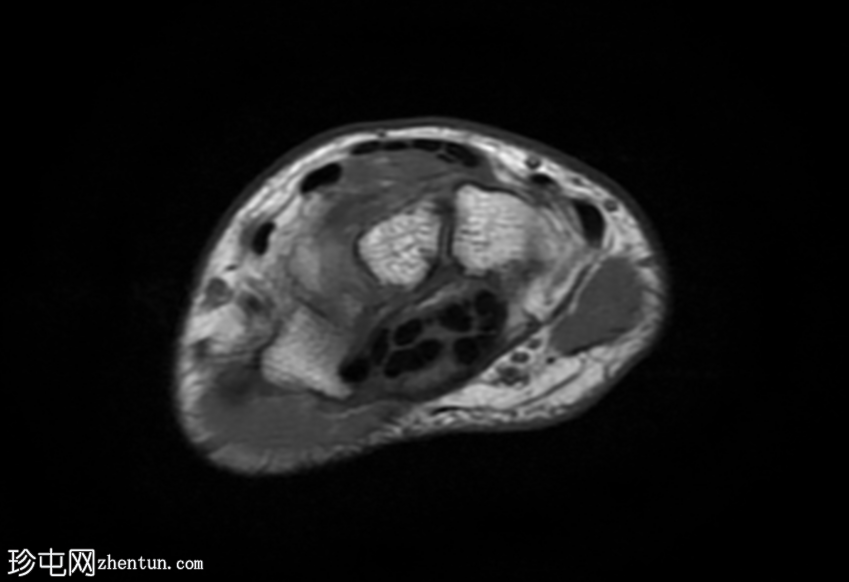

MRI

轴位

T2加权像

T1加权像

腕背多房性腱鞘囊肿(轴位、矢状位和冠状位图像均可见),位于伸肌腱下方的腕背关节囊内,提示为腕背腱鞘囊肿。

该病例展现了腕背腱鞘囊肿的典型

影像

学表现和位置。